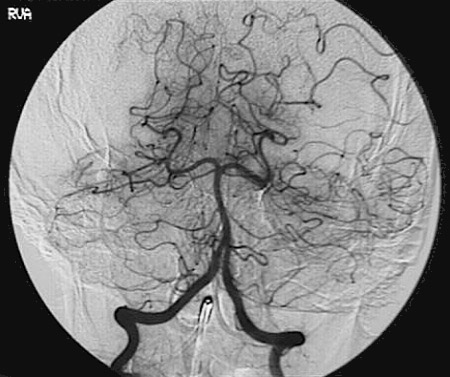

Identify the following arteries in the cerebral angiogram by clicking in the image below:

Vertebral Arteries - Basilar Artery